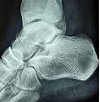

Radiography of the ankle joint.

Рентгенография голеностопного сустава

Рентген голеностопного сустава. Радиационная техника используется для оценки состояния костных структур, которые образуют лодыжку. В травматологии его используют при подозрении на переломы лодыжки, таранной кости и пяточной кости, остеомиелит и переломы лодыжки. В других областях медицины его назначают при врожденных и приобретенных уродствах, артритах, новообразованиях, дегенеративно-дистрофических процессах. Обычно производится в двух проекциях, не требует специальной подготовки. При отсутствии экстренных показаний у детей и женщин в течение периода беременности, если это возможно, их заменяют другими методами (например, КТ).